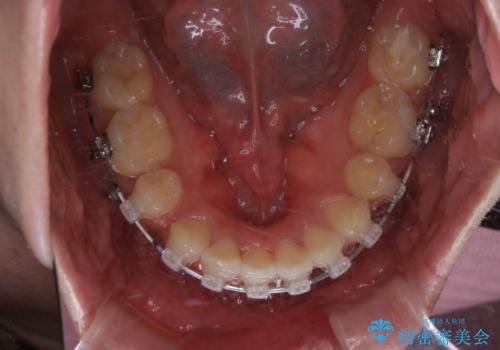

がたつき、口ゴボ(出っ歯)、真ん中のずれを抜歯矯正治療で治す。ワイヤー矯正治療

- 矯正装置

- ワイヤー矯正 審美装置

- 治療計画

- 口元の突出感とがたつきを気にして来院されました。

突出感とがたつきの改善を行うために大きなスペースが必要であったため、親知らず以外の歯を4本歯を抜歯する計画を立てました。

移動量が大きいこと、また、患者さんの生活習慣的にマウスピース装着が難しそうとの理由から

ワイヤー表側矯正装置で治療を行うことになりました。

もともとの歯の根っこの位置の関係で、治療途中において上下の真ん中の位置がずれてしまいました。機能的には問題ありませんが患者様と相談し、期間を延ばした上で真ん中を合わせる治療を追加で行いました。